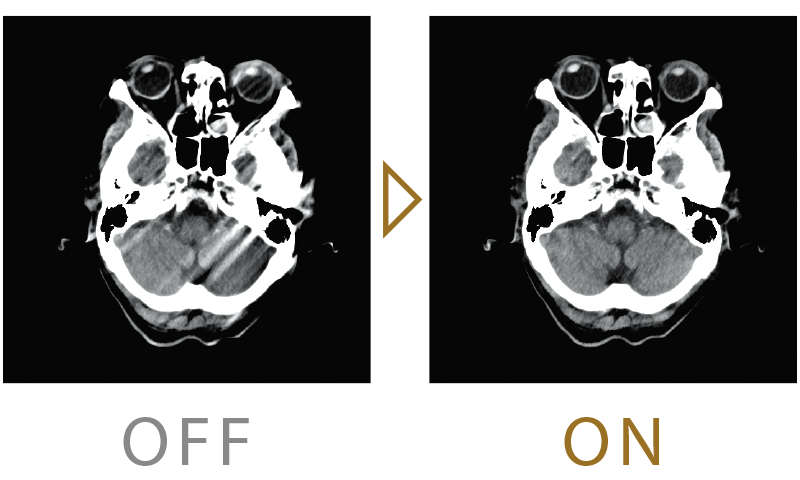

Noise reduction strength can be selected from 7 levels. We provide high-quality images by reducing image noise and artifacts with an appropriate exposure dose according to the facility's operation policy.